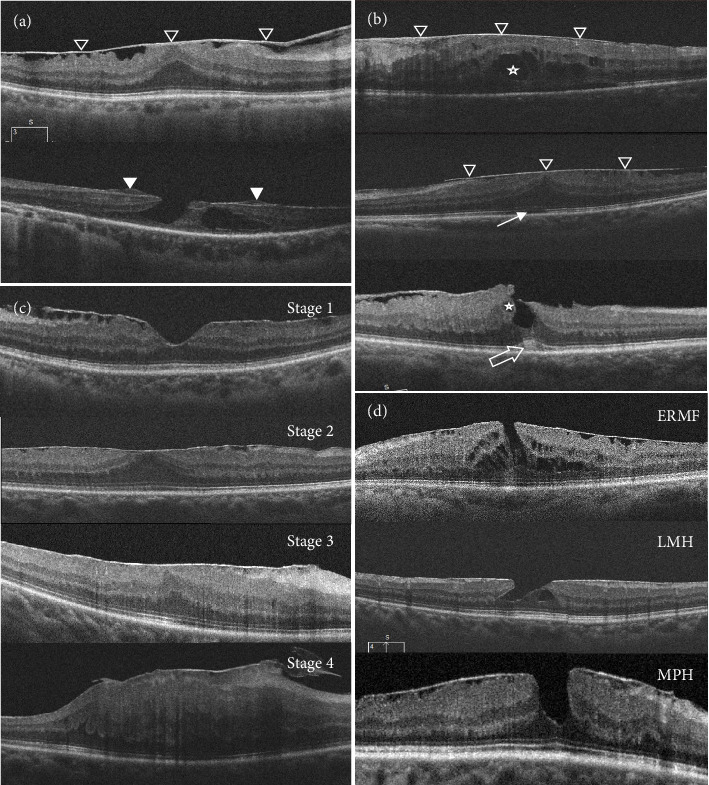

目的:在临床实践中,一些术前诊断为“特发性视网膜前膜(idiopathic epiretinal membrane, iERM)”的眼睛,一旦发现周围视网膜孔洞,就会被修正为“继发性视网膜前膜(secondary epiretinal membrane, sERM)”。本研究利用光学相干断层扫描(OCT)图像比较了视网膜外周孔(PRH)引起的iERM和sERM的特征。方法:采用回顾性横断面研究方法,对635只行玻璃体切割伴玻璃体膜剥离手术的眼进行研究。将发现视网膜外周孔洞的115只眼(18.1%)分配给sERM-PRH组,520只眼分配给iERM组。比较两组患者的人口学资料和OCT特征。此外,所有的眼睛都采用双重分级方案进行评估:将ERM进展严重程度分为四个阶段,并在解剖学上分为三种与ERM相关的部分厚度黄斑孔。结果:两组患者在年龄、性别、症状持续时间、眼轴长度、最佳矫正视力等方面无显著差异。黄斑中心厚度、感光器内外节连接线缺损比例、视网膜内积液、棉球征、视网膜前增生等OCT特征也无差异。然而,在iERM组中观察到颞和鼻象限之间的中央凹旁厚度的天然差异,而在sERM-PRH组中消失。此外,两组之间的眼睛在两个分级量表上分布相似。结论:我们的研究结果表明,即使是OCT图像也很难提供早期区分sERM和iERM的有效线索,这突出了临床医生在术前和术中对周围视网膜进行彻底的眼底检查的必要性。

Purpose: In clinical practice, some eyes preoperatively diagnosed with "idiopathic epiretinal membranes (iERM)" will be amended to "secondary epiretinal membranes (sERM)" once peripheral retinal hole is detected. This study utilized optical coherence tomography (OCT) images to compare the characteristics between the iERM and sERM due to peripheral retinal hole (PRH). Methods: In this retrospective, cross-sectional study, 635 eyes that had undergone pars plana vitrectomy with membrane peeling were enrolled. A total of 115 eyes (18.1%) detected with peripheral retinal holes were allocated to the sERM-PRH group while the other 520 eyes were to the iERM group. The demographic data and OCT characteristics were compared between the two groups. Besides, all the eyes were evaluated by a double-grading scheme: severity grading of ERM progression into four stages plus anatomical classification into three kinds of part-thickness macular holes associated with ERMs. Results: No significant difference was found in age, gender, symptom duration, axial length, or best-corrected visual acuity between the two groups. There was also no difference concerning the features based on OCT, ranging from central macular thickness, the ratios of the photoreceptor inner/outer segment junction line defect, intraretinal fluid, cotton ball sign, to epiretinal proliferation. However, the native difference in parafoveal thickness between the temporal and nasal quadrants was observed in the iERM group, yet disappeared in the sERM-PRH group. Moreover, eyes between the two groups were distributionally similar in both grading scales. Conclusion: Our results demonstrated that even OCT images could hardly provide effective clues for early differentiating sERM from iERM, which highlighted the necessity of a thorough pre- and intro-operative fundus examination of the peripheral retina for clinicians.